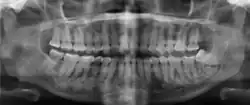

| Florid osseous dysplasia of the mandible | |

| Diagnostic method | X-ray, CBCT scan, vitality testing of teeth |

Diagnosis is based on clinical and radiographic observations, and in rare cases, biopsy may be performed.[3] Diagnosis is important so that the treating doctor does not confuse it for another periapical disease such as rarefying osteitis or condensing osteitis. Incorrect diagnosis could lead to unnecessary root canal treatments, or biopsy or surgical intervention which can be invasive and increase the risk of infection.[5] A pulp vitality test such as a cold test or electric pulp test can aid in diagnosis, since COD generally does not compromise pulp vitality.[6] COD can be found in individuals of all ages and ethnic backgrounds, but it has been observed more frequently in individuals of African, East Asian, and Asian descent.[7] Cone-beam computed tomography (CBCT) has proven useful in distinguishing between COD and periapical cysts, when examined with quantitative texture analysis using specialized software.[5]